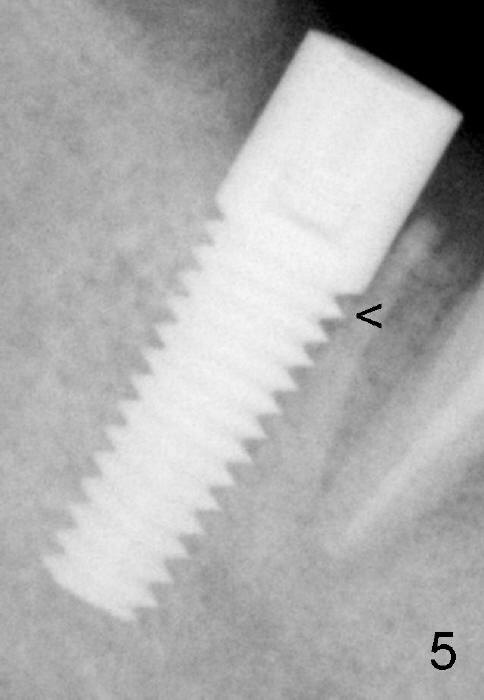

Three and a half months postop, the bone grows into the threads of the implant (Fig.5 <, as compared to the same area of Fig.3,4 (immediately postop).